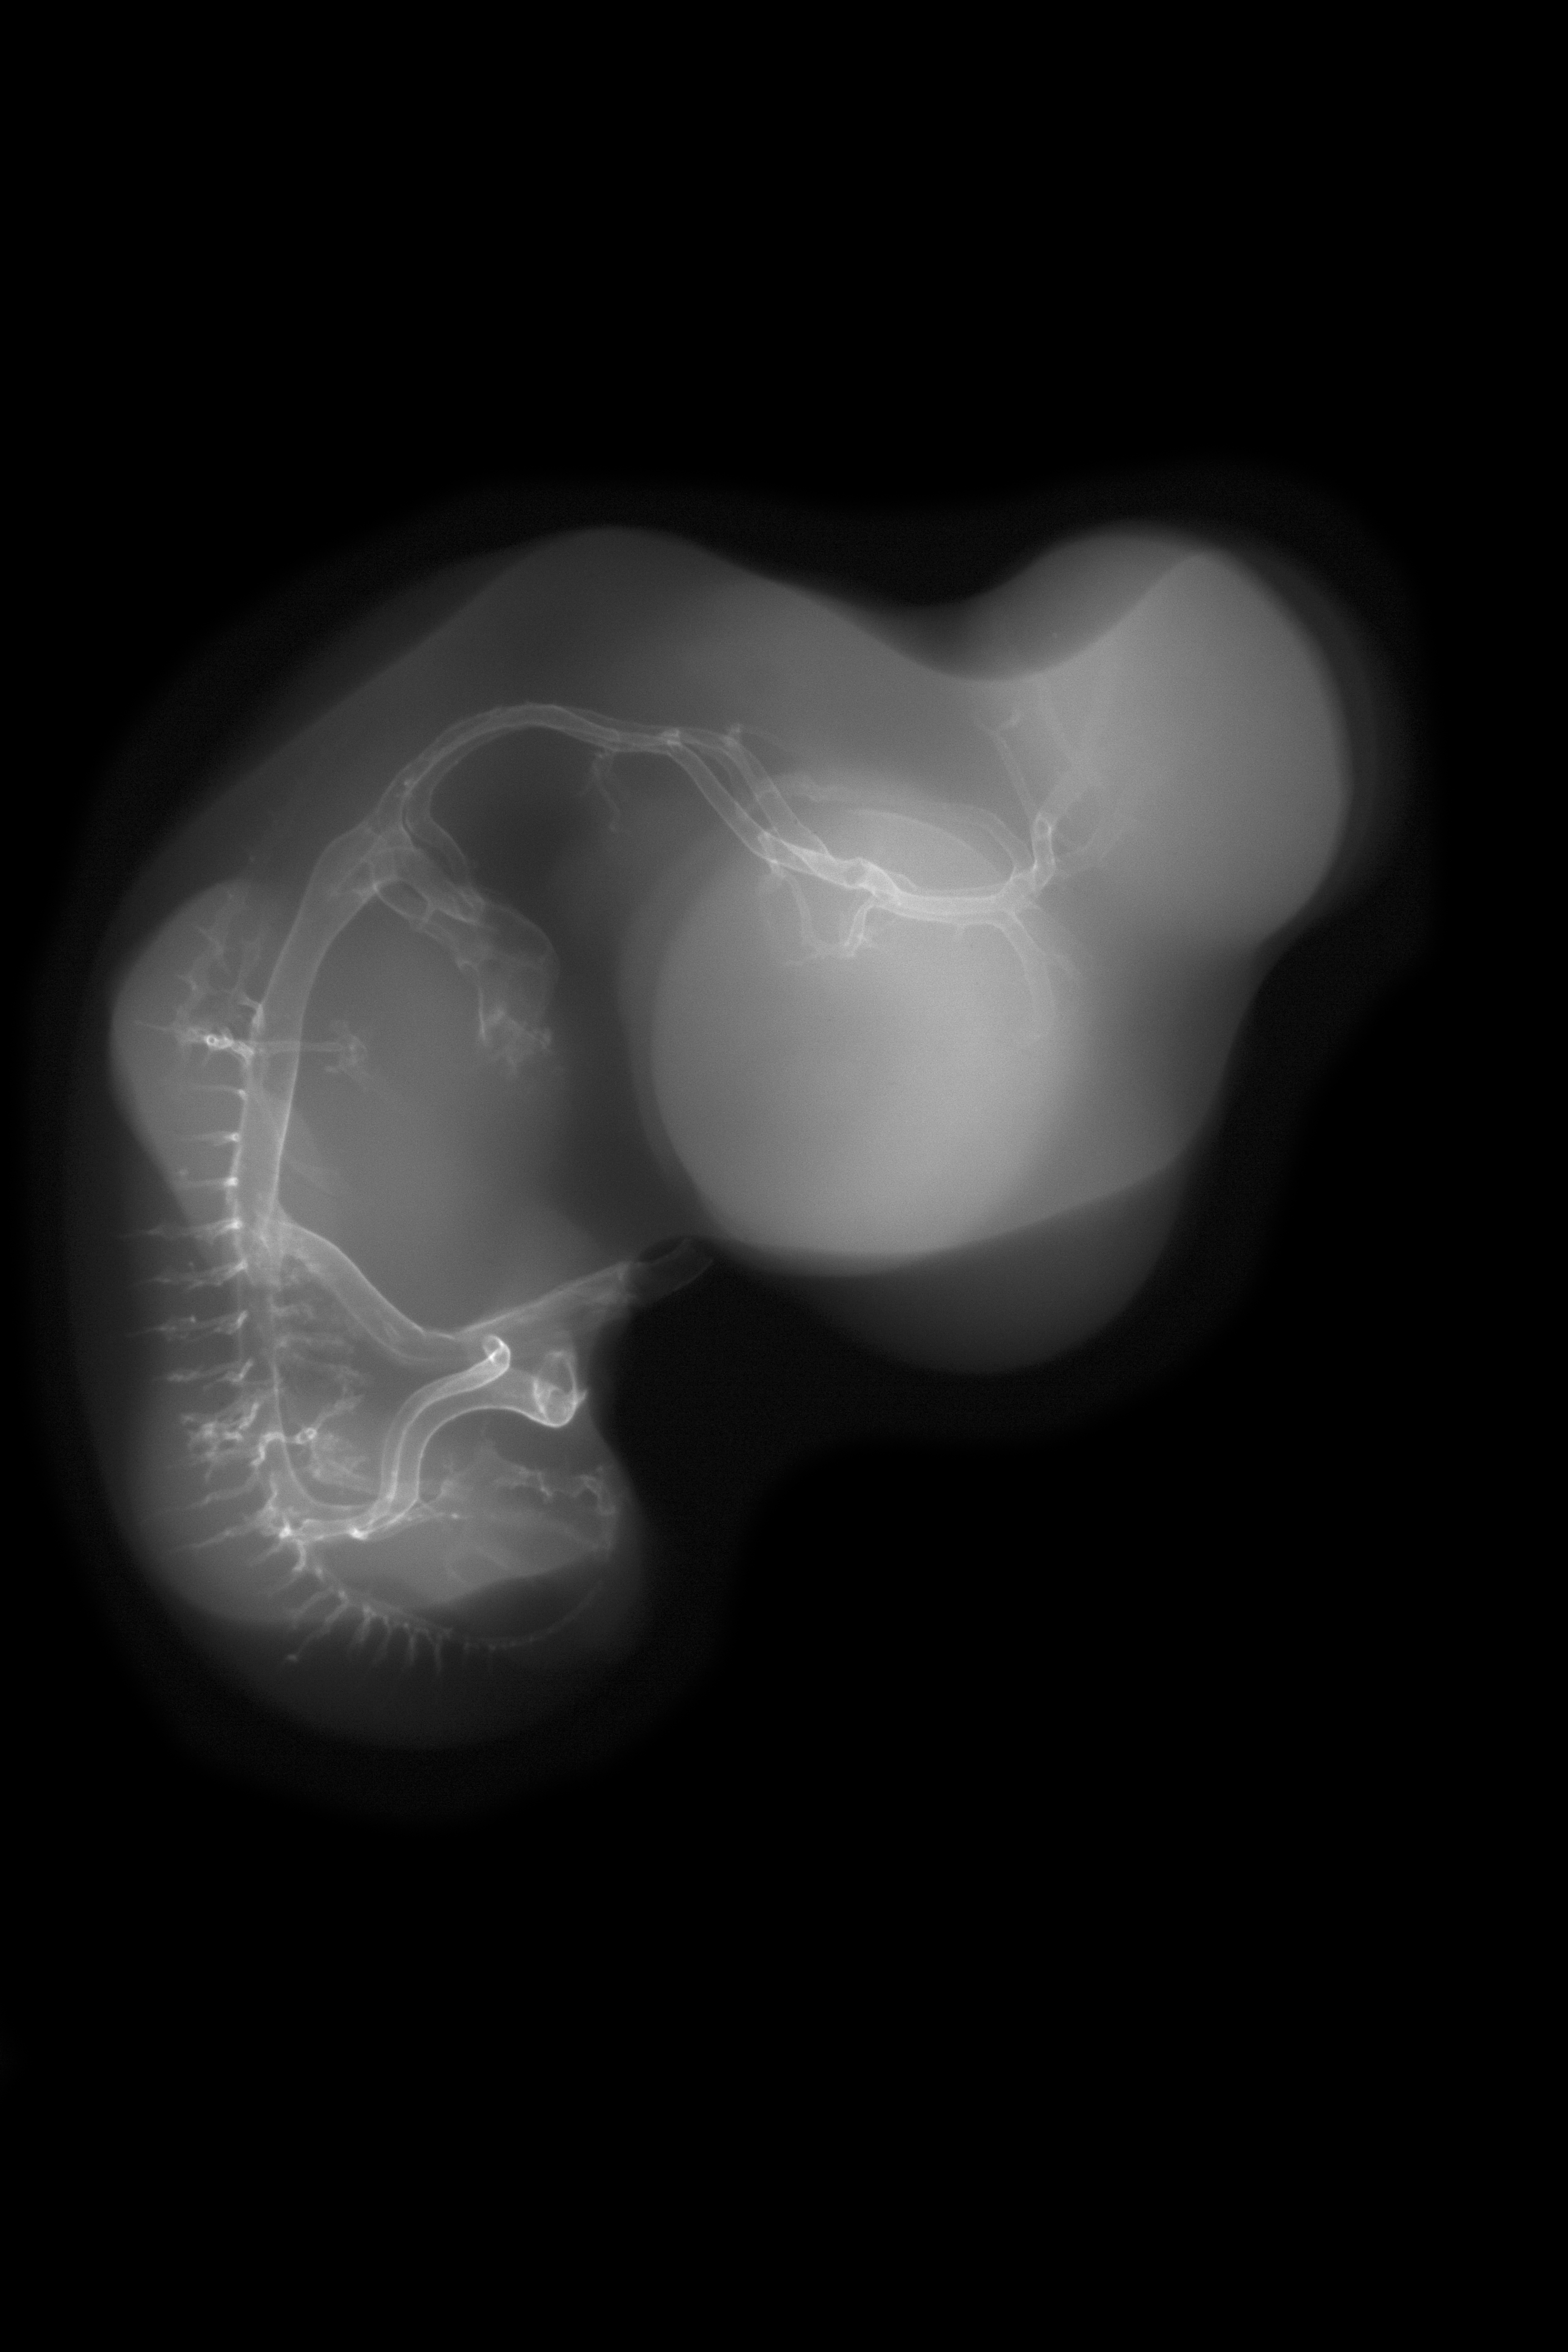

Chick Embryo Microangiography

Hamburger-Hamilton (HH) Stage 28 (approx. 5.5 - 6 days)

X-Ray Micrographs